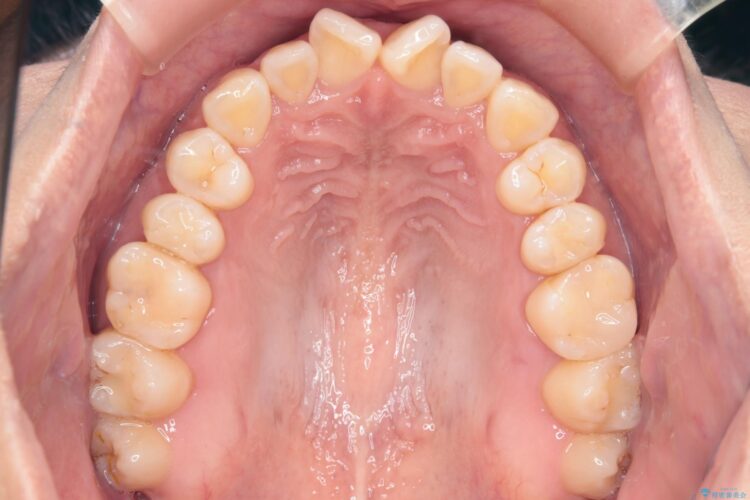

上の前歯のねじれが気になるとご来院された患者様です。

前歯の捻れとがたつきを改善するために、IPR(歯と歯の間を削る処置)と歯列拡大をすることで歯並びを整えていく治療計画を立てました。